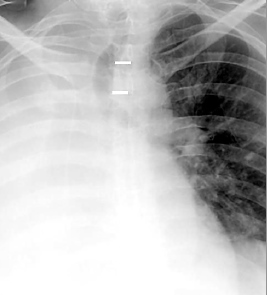

Помимо опроса и объективного осмотра, включающего перкуссию и аускультацию грудной клетки, проводят рентгенологическое исследование в двух положениях тела (в 2-х проекциях). Это основной метод обнаружения ателектазов легких.

На рентгеновских снимках выявляют следующие признаки, указывающие на спадение легочной ткани:

Однородное затемнение в области поражения. Размеры тени зависят от вида ателектаза: при долевом выявляется обширное затемнение, при сегментарном — в виде клина или треугольника, расположенного вершиной к корню легкого, дольковые ателектазы множественные и похожи на очаговую пневмонию. Дистензионный ателектаз расположен низко, около диафрагмы, имеет небольшие размеры и вид поперечных полос или темных дисков. Смещение органов: при компрессионном ателектазе смещение наблюдается в здоровую сторону, так как на стороне поражения давление больше, при обтурационном, наоборот – смещение будет в сторону ателектаза, так как на стороне поражения нарастает притягивающее отрицательное давление. Подъем купола диафрагмы – это видно по расположению печени.

Если диагноз непонятен, рентгенологическое обследование дополняют компьютерной томографией. При перекрытии просвета бронхов выполняют бронхоскопию – осмотр по ходу бронхов с помощью зонда с камерой, который вводят в дыхательные пути.

Во время инструментальных диагностических манипуляций важно не только установить наличие ателектаза и его точную локализацию, но и уточнить объем спавшейся ткани, чтобы определить правильную тактику лечения и объем лечебных манипуляций. На рентгенограмме для диагностики ателектаза имеет значение состояние не только ткани легких, но и корней легких, ребер, органов средостения, купола диафрагмы, плевры, плевральной полости и даже позвоночника (будет наблюдаться его сколиотическое отклонение в направлении выпуклости в сторону пораженного легкого)

На рентгенограмме для диагностики ателектаза имеет значение состояние не только ткани легких, но и корней легких, ребер, органов средостения, купола диафрагмы, плевры, плевральной полости и даже позвоночника (будет наблюдаться его сколиотическое отклонение в направлении выпуклости в сторону пораженного легкого).